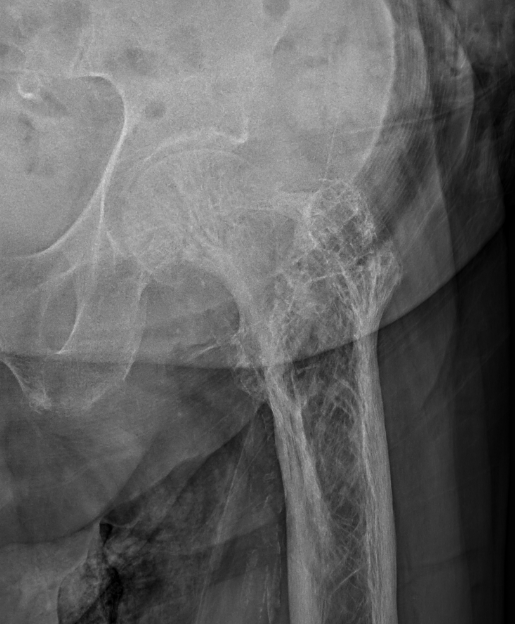

Femur

Tibia

Tibia deformity - sabre tibia

Xray

Findings

- mixed lysis and sclerosis

- cortical thickening

- bone expansion and deformity